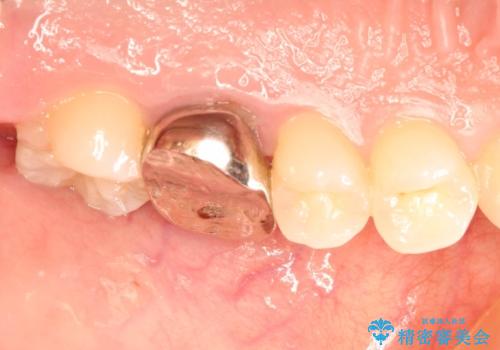

金属の奥歯 → 白い奥歯 根管治療からのやり直し

- 再根管治療→土台の築造 を行った上でのかぶせ物のやり替えをおこないました。

神経の無い歯のかぶせ物をやり替える際は、是非根管治療からしっかりやり直すことをおすすめします。